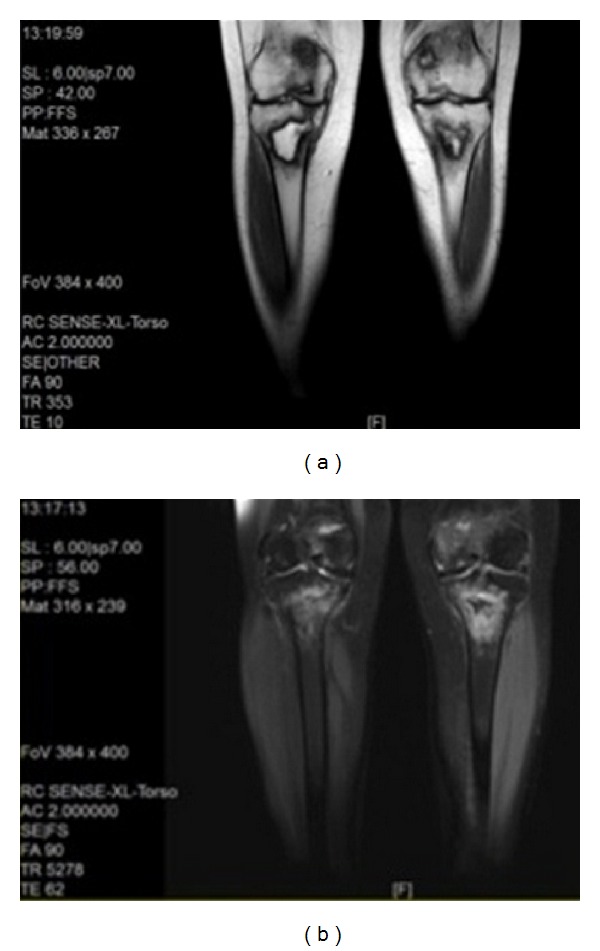

Magnetic resonance imaging revealed bilateral signal changes in distal femurs and metaphyseal-diaphyseal region of tibias that were consistent with bone infarctions in these areas (Figures 2(a) and 2(b)).

Figure 2.

Signal changes in distal femur and metaphyseal-diaphyseal region of tibia consists with bone infarction in T1 (a) and T2 (b) weighted images.